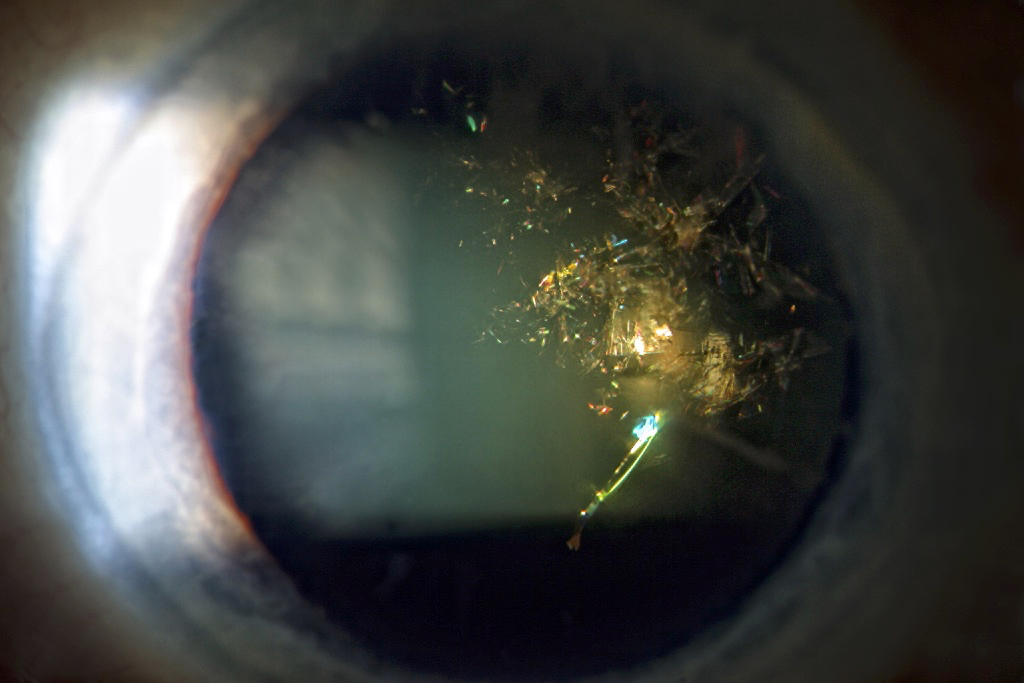

Christmas Tree Cataract Eye Wiki . christmas tree cataract is typically idiopathic or associated with myotonic dystrophy. the christmas tree cataract is a rare type of polychromatic cataract. while cataracts themselves are common, christmas tree cataracts are a rare subtype of cataract. Although it is not often responsible of significant visual loss, it can. a diagnosis of acute conjunctivitis in both eyes with a christmas tree cataract (ctc) and early cuneiform.

while cataracts themselves are common, christmas tree cataracts are a rare subtype of cataract. a diagnosis of acute conjunctivitis in both eyes with a christmas tree cataract (ctc) and early cuneiform. the christmas tree cataract is a rare type of polychromatic cataract. christmas tree cataract is typically idiopathic or associated with myotonic dystrophy. Although it is not often responsible of significant visual loss, it can.